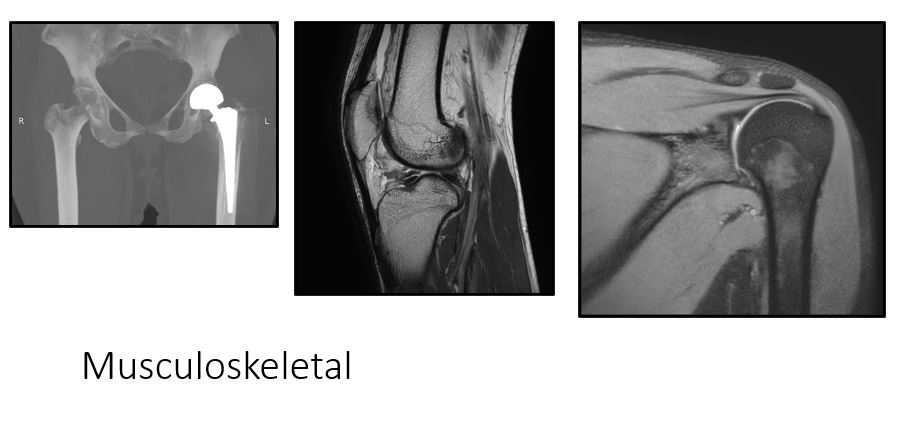

Musculoskeletal imaging & interventions:

- State of art 3T MRI scanner with dedicated extremity coils offering high resolution imaging of joints , spine and soft tissues.

- High resolution Ultrasound for dedicated musculoskeletal imaging and interventions

Diagnostic:

- Digital radiography (X-ray)

- Computerized tomography (CT scan)

- CT Arthrography

- Magnetic Resonance Imaging (MRI)

- Metal artefact reduction software (MARS)

- MRI Arthrography – Shoulder, elbow, wrist, hip , knee joints

- Musculoskeletal Ultrasound – joint, ligament, tendon, nerve imaging, High resolution imaging of soft tissue lesions.

- Sports trauma imaging